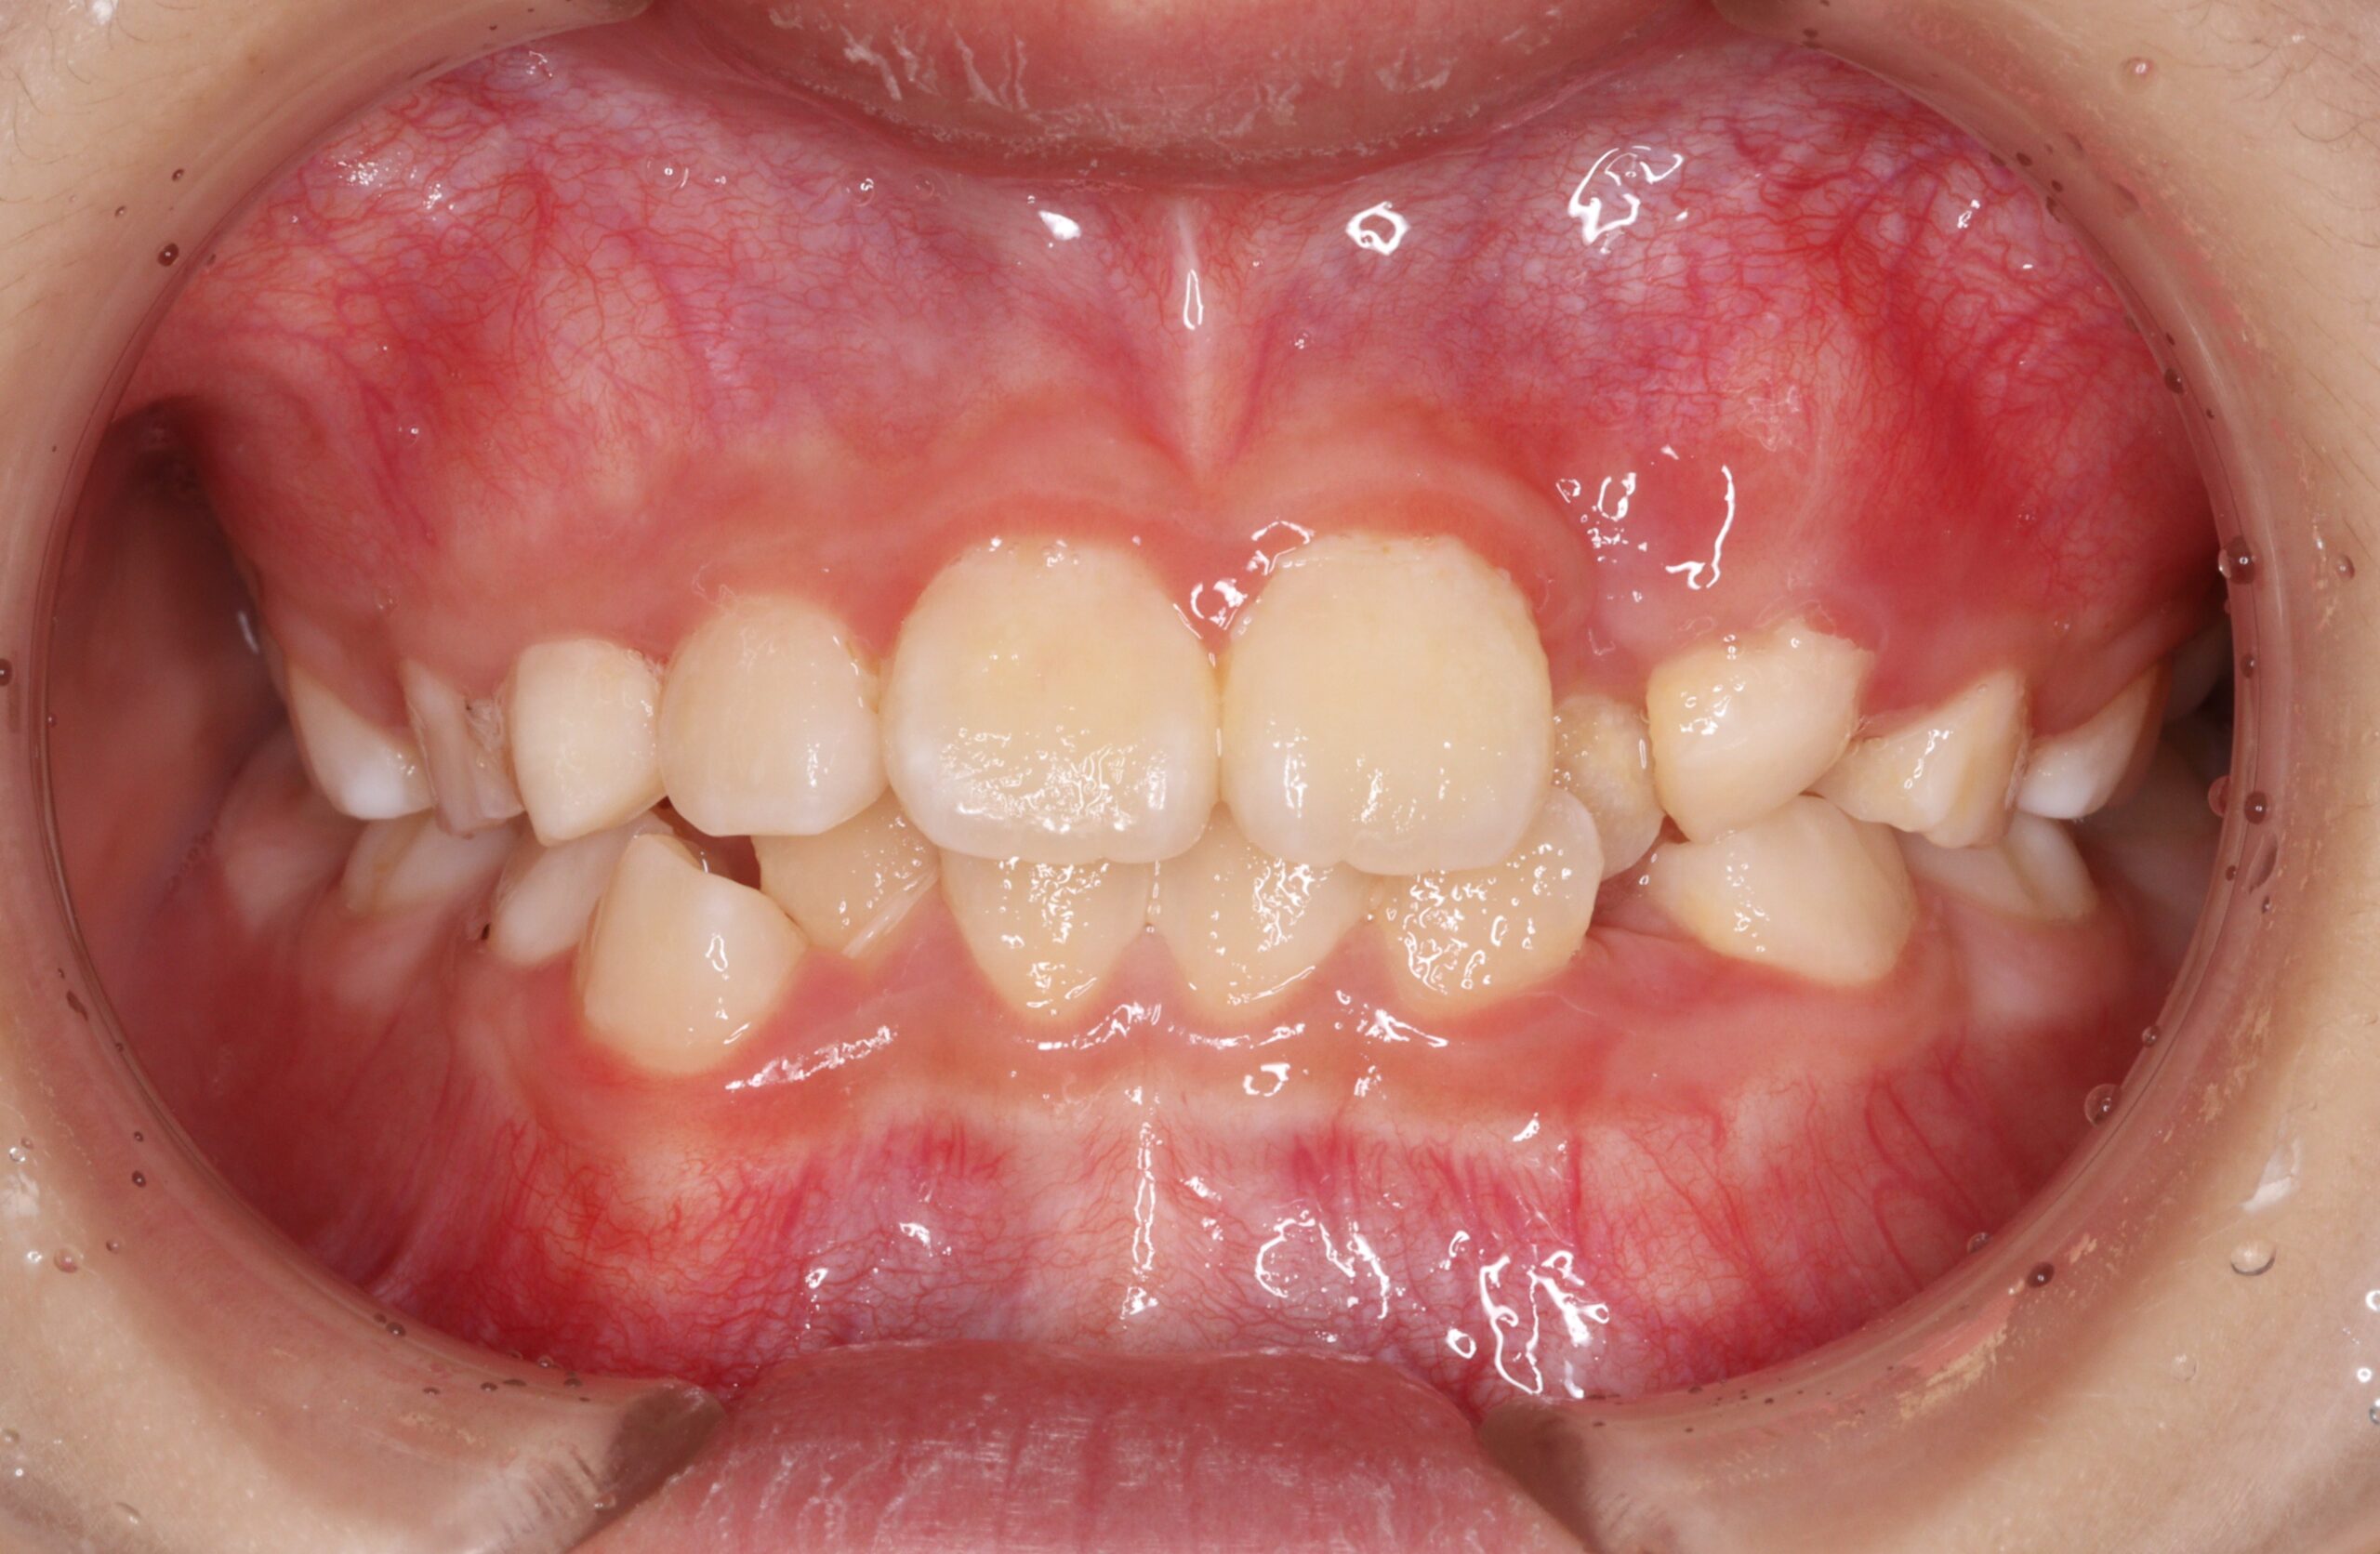

矯正術前:正面

今回ご紹介する患者様は、全体的な歯並びのがたつきを気にされており、矯正検査後叢生Ⅰ級と診断いたしました。

| 主訴 | 全体的な歯並びのがたつきが気になる |

| 治療内容 | 患者様は全体的な歯並びのがたつきを気にされており、矯正検査後叢生Ⅰ級と診断いたしました。 |